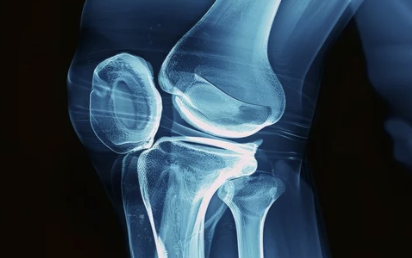

✔ 퇴행성 관절염이 심해지면 무릎 연골이 닳아 뼈끼리 부딪히며 심한 통증 유발

✔ 일상생활이 어려워지고 걷기조차 힘들어질 수 있음

✔ 수술을 통해 손상된 관절을 인공관절로 대체하면 통증 완화 & 활동 가능

✔ 하지만, 수술비가 평균 300~500만 원 정도로 부담이 클 수 있음